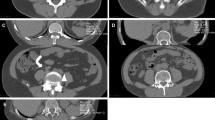

All procedures were performed or supervised by an attending radiologist. Patients were positioned at the discretion of the operator based on characteristics of the renal mass such as the size of the lesion, the location within the kidney and the location of adjacent organs. Moderate sedation was administered. A General Electric LightSpeed Xtra (GE Healthcare, Milwaukee, WI) 80 cm wide-bore 16-slice MDCT scanner was used for both the phantom experiment and the clinical procedures. A limited non-contrast CT scan through the kidneys was routinely performed for planning purposes. After administration of local anesthesia, CT fluoroscopic guidance was utilized for probe insertion (Perc24, Endocare Inc, Irvine, A). The kVp was typically set to 120, while the mAs was set to 50–100 at the discretion of the operator, according to the size of the patient. The number of probes utilized was also at the operator’s discretion. Administration of intravenous contrast material with an additional limited diagnostic CT through the kidneys was performed at the discretion of the operator when visualization of the lesion was difficult on the preliminary non-contrast CT. When adjacent organs such as bowel were in excessively close proximity to the lesion, hydrodissection was performed by introducing an 18-gage needle interposed between the kidney and the organ using CT fluoroscopic guidance followed by infusion of 100–300 mL of saline until an adequate buffer zone was achieved. A 10 min freeze −8 min thaw −10 min freeze cycle was conducted. After removal of the probes, a repeat non-contrast diagnostic CT scan through the region of the kidneys was performed to assess for complications such as hematoma or pneumothorax and for assessment of the cryoablation zone.

Organ dose measurements

In the prone position during the pre-procedure scan, the highest organ dose was measured in the skin. In the decubitus position during the pre-procedure scan, the highest dose was measured in the pancreas and stomach. In the prone position during fluoroscopy, the highest doses were recorded in the skin, kidneys, pancreas, and liver. With the CT gantry tilted, there was no significant difference in dose recordings in the specified organs compared to no gantry angulation. In the left lateral decubitus position, the highest doses were recorded in the skin, liver, and pancreas. Compared to the prone position, there was a significant decrease in dose to the dependent left kidney with left lateral decubitus positioning.

We believe this to be the first report that quantifies absorbed organ radiation doses during CT fluoroscopy-guided cryoablation procedures of solid renal tumors. The organs directly in the field of fluoroscopic view (liver, spleen, kidneys, pancreas, and adrenals) have the overall highest absorbed doses, as expected. In the left lateral decubitus position, the liver had the highest overall absorbed dose, which was higher than the absorbed dose in the prone position. There is likely a small amount of absorption of photons by the CT table, which decreases the dose for dependent organs and increases the dose for nondependent organs. Furthermore, for certain positions, such as lateral decubitus, there is an added effect of certain organs being closer to the x-ray tube.